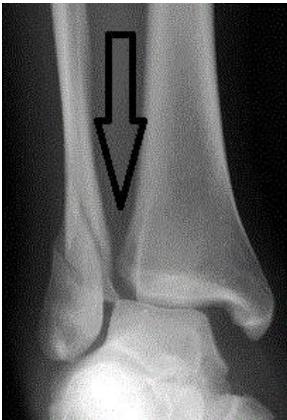

Medial Clear Space

- Normal: < 4-5 mm (mortise view)